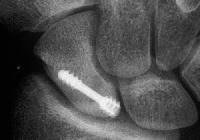

Xray before

Click for larger image

and two months postop: